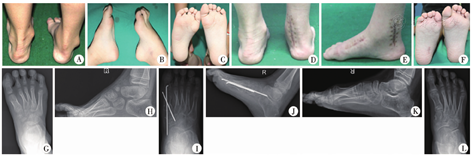

本组病例术后随访时间平均32(24~48)个月,表1结果显示,患儿手术后跟骨轴线、Meary角、Pitch角、Hibb角和疼痛不适症状较手术前有明显改变,差异均有统计学意义(均P<0.05)。依据Wicart高弓足评分方法,本组疗效优13足、良3足、可2足。典型病例手术前后照片见图3A至图3L。

注 A、B、C:高弓内翻足畸形患儿手术前双足大体照片;D、E、F:右侧高弓内翻足畸形患儿术后双足大体照;G、H:为右侧高弓内翻足畸形患儿右足手术前X线片;I、J:为右侧高弓内翻足畸形患儿右足术后3个月X线片;K、L:为右侧高弓内翻足畸形患儿右足术后2年X线片